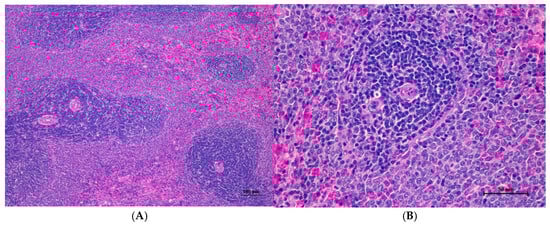

Figure 9.

Histopathological examination of rat splenic tissue in sub-acute toxicity from daily (28 days) fed oral dose of CDF showed normal microscopic appearances. (A) Splenic tissue exhibited well-organized white pulp, marginal zone, and red pulp (100×, H&E). (B) High magnification showed an unremarkable lesion of red pulp. The lymphoid follicle displayed an intact germinal center with densely packed lymphocytes (400×, H&E).

Histopathological analysis of rat organs following 28-day cassava fiber administration revealed mild hepatocellular swelling and vacuolation in the liver, deemed within normal limits, while the kidneys, heart, and spleen exhibited no significant lesions; however, the lungs consistently displayed moderate to severe alveolar edema, septal engorgement, hemorrhage, and inflammatory cell infiltration, suggesting a potential pulmonary response to the cassava fiber, despite the absence of overt clinical toxicity.

Rats of both sexes, with respect to histopathological changes in the liver, kidney, heart, and spleen, were normal. Histopathological changes in the liver, including hepatic vacuolation and hepatic degeneration, were found in all groups of both sexes. These changes were found to be abnormal in the cytoplasm of liver cells, to a mild degree and diffuse in some areas of the liver, and portal tracts were normal. These findings represent only minimal and non-significant pathologic changes. Additionally, biochemical values were within normal limits, indicating this organ remained normal.